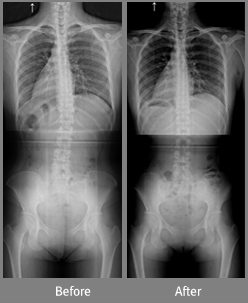

[16세 여학생 : 3개월간 30회 교정치료]Before 구부정한 자세로 오랜 시간을 앉아있기 힘들고 허리통증을 호소하자 부모님과 내원 After 30회 교정치료 후 통증 및 상태 호전 자세불균형 치료시스템